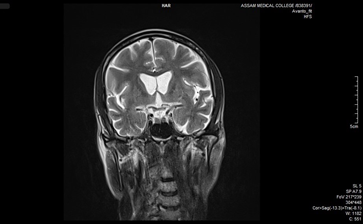

Skull bone marrow plays a critical role in central nervous system (CNS) immunity by housing specialized immune cells that interact directly with cerebrospinal fluid (CSF), influencing neuroinflammation and neurodegeneration. Unlike peripheral marrow, skull marrow uniquely contributes to brain immune responses. Non-invasive imaging techniques such as TSPO-PET show strong potential for detecting skull marrow activity in conditions like Alzheimer’s and multiple sclerosis, offering an alternative to invasive bone marrow biopsies (Table 3). Additionally, intracalvarial drug delivery, which bypasses the blood-brain barrier, significantly enhances therapeutic delivery to the brain. This emerging approach holds promise for improving treatment outcomes in CNS disorders and warrants further investigation.